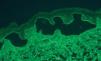

A pesar de presentar todos los pacientes lesiones características de PM, sólo en un caso se encontró IFD positiva en la biopsia de la piel (paciente 3). En 2 casos con IFD negativa la IFI fue positiva para IgG, con unos valores de 1:320 y 1:80. En 2 casos la IFI fue positiva mediante salt-split. En uno de ellos se observó únicamente positividad para IgG con un título de 1:80, con depósitos lineales en el lado epidérmico (fig. 2). En el otro, se encontró positividad con un título de 1:640 para IgG, y de 1:160 para IgA (fig. 3), con depósitos lineales en el lado epidérmico (tabla 1).

Fig. 2.--Depósitos lineales de autoanticuerpos IgG en la unión dermoepidérmica en el PM. La técnica de salt-split se realizó con piel humana en cloruro sódico 1M. Los anticuerpos anti-IgG humana marcan el lado epidérmico de la ampolla formada artificialmente (flechas) (paciente 4) (x200).